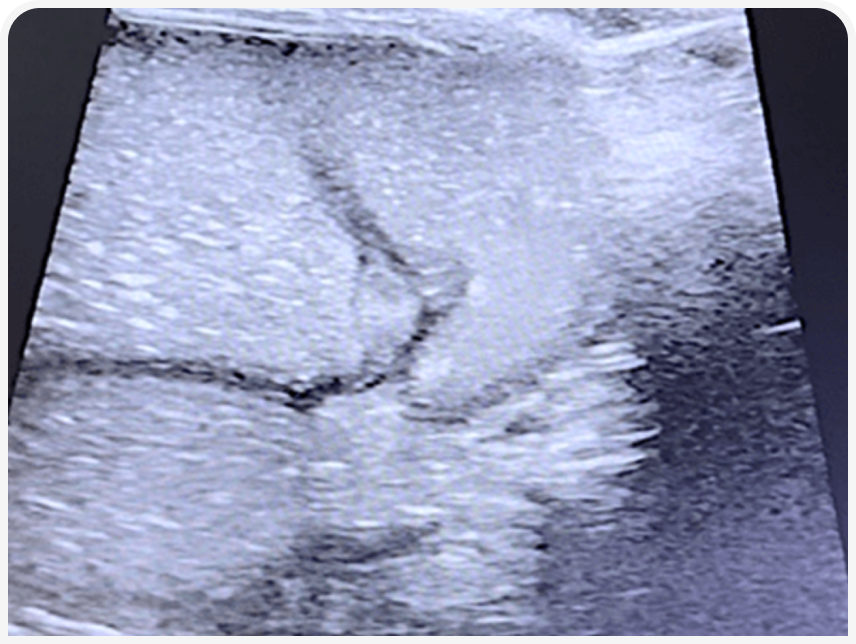

Для диагностики данного состояния оптимально использовать УЗИ. При ультразвуковом исследовании ЖКТ у плода или новорожденного будут выявляться «классические» признаки механической обструкции кишечника — расширение петель кишечника и желудка значительным количеством жидкостного содержимого до места обструкции и нормальная картина без расширения просвета после места обструкции.

Особое значение имеет УЗИ плода на поздней стадии беременности. По опыту автора, врожденную ВКН достаточно точно удается диагностировать у плодов на последней неделе беременности. У плодов при внутриутробном развитии может визуализироваться жидкость только в желудке.

При патологии будет обнаруживаться картина расширения петель тонкого кишечника, что с высокой долей вероятности коррелирует с ВКН на любом уровне ниже пилорического отдела желудка. При сомнениях полезно сравнить картину подозрительного плода и других плодов.